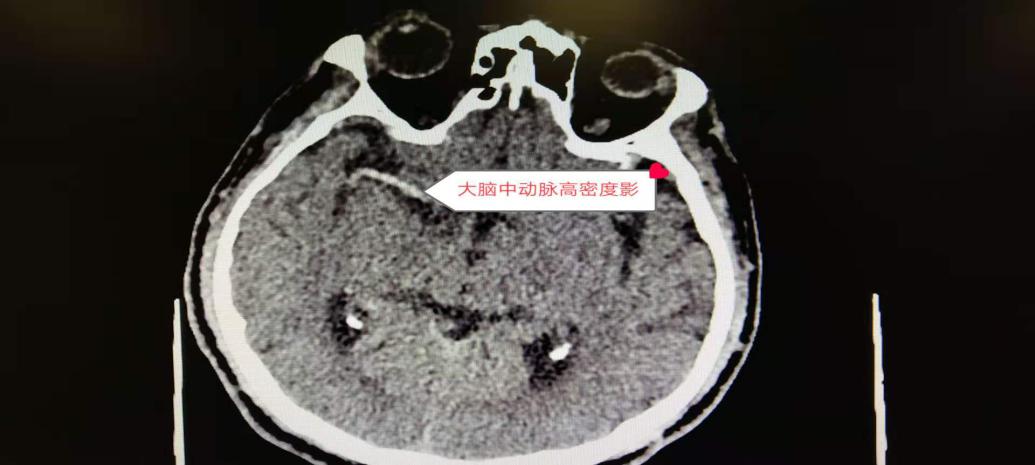

CT检查结果显示:该患者右侧大脑中动脉高密度影、中动脉有血栓,符合脑梗症,状随时有生命危险,需立即进行介入取栓手术。本着生命至上救人第一的原则我院即刻为该患者开启生命绿色通道,介入血管外科主任张煜杰立即召集科室大夫并联系导管室为患者进行造影取栓。